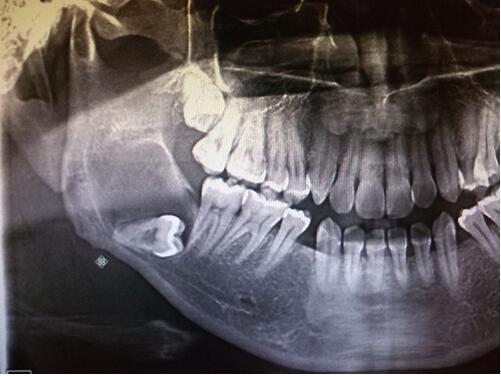

5、阻生齿

通常这是最讨厌的一种,牙医会觉得很难搞定,但患有者却不一定有感觉,一般需要拍片才能看得出来了,所以患有者容易忽略。这一种类型的牙齿,通常埋在齿槽骨的里面,如果会痛,或是诊断会有病灶发生的时候,就需要拔除了。